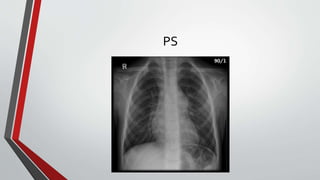

Chest Radiography

• The classic radiographic features are cardiomegaly(from right atrial and

right ventricular enlargement),

• Dilated central pulmonary arteries with pulmonary plethora indicating

increased pulmonary flow, and a small aortic knuckle (reflecting a chronic

low–cardiac output state).

PS

• Increased pulmonary arterial vascularity extends to the periphery of the lung fields

• The pulmonary trunk and its proximal branches are dilated The left branch is

usually obscured by an enlarged pulmonary trunk , but the lateral view discloses

dilation of both branches

• The ascending aorta is seldom border forming because the intracardiac shunt does

not traverse the aortic root .

• In young adults with pulmonary vascular disease and a balanced or reversed shunt,

the pulmonary trunk and its branches are strikingly enlarged and calcified (Right

atrial enlargement is characteristic